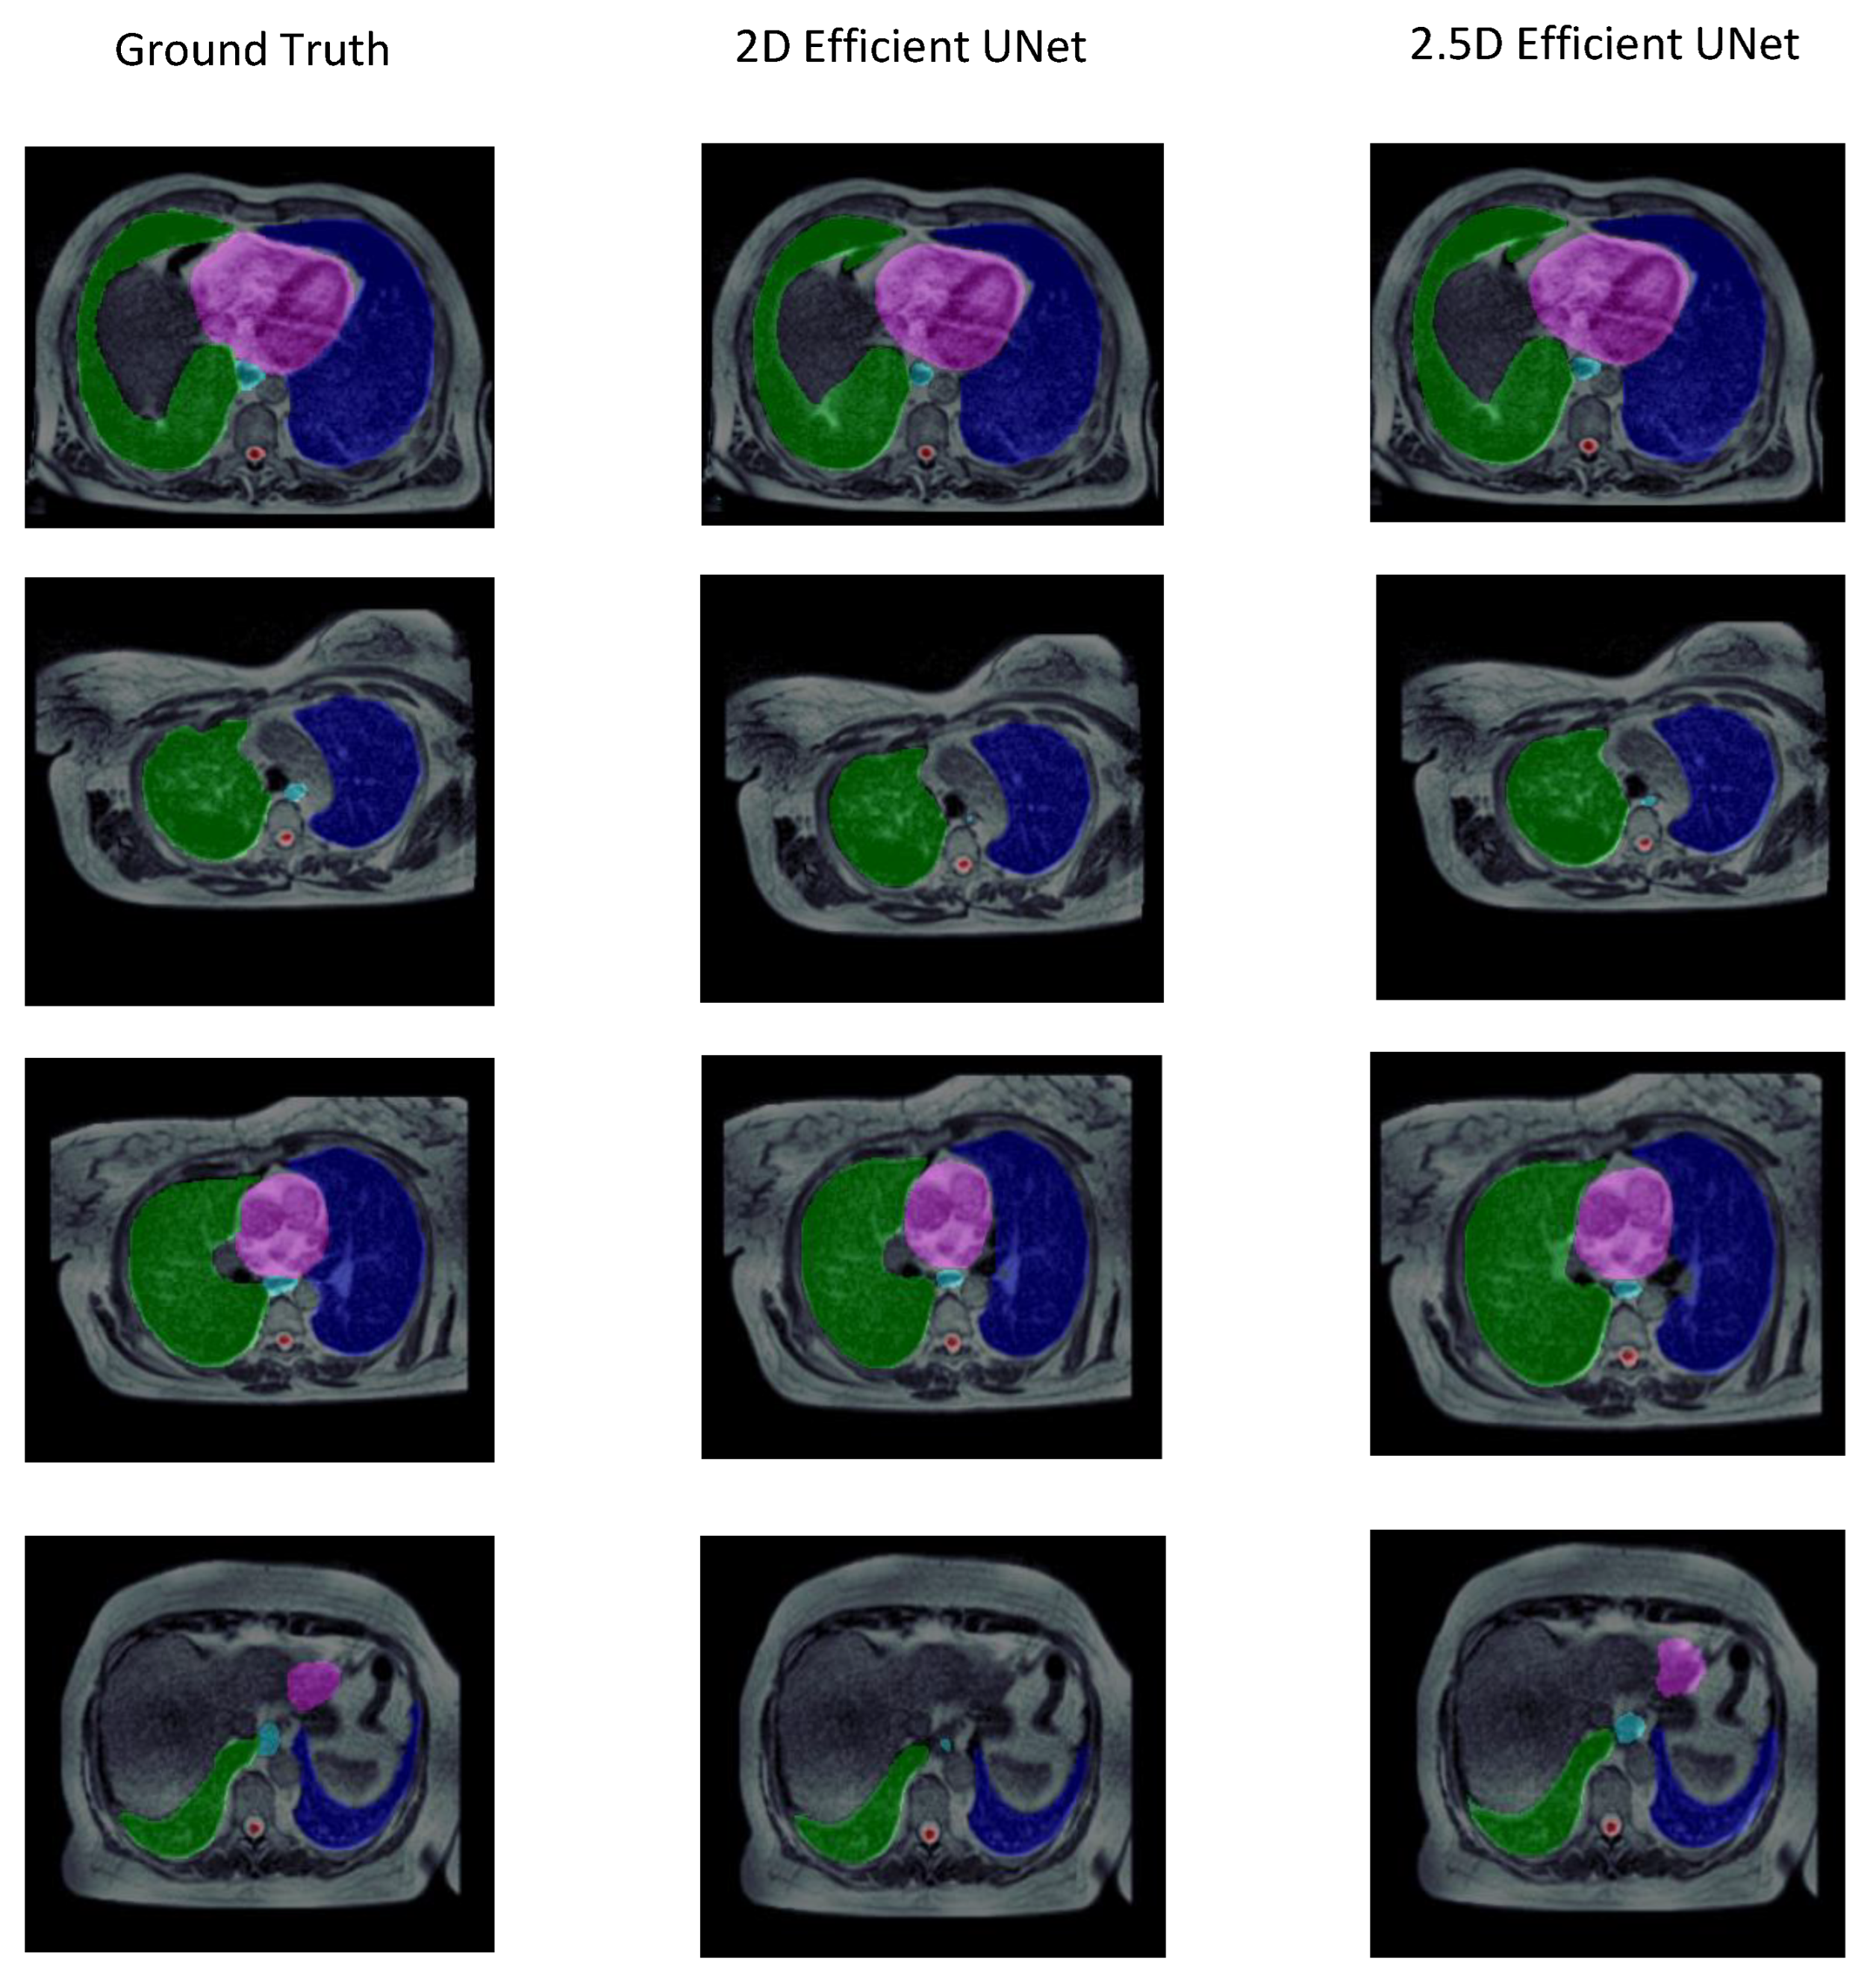

3.2. Experiment 2: Training Strategy Selection

| 2.5D | 0.820 ± 0.041 | 0.725 ± 0.052 | 10.353 ± 4.974 | 153.943 ± 50.149 | 0.734 ± 0.090 |

| 2D | 0.804 ± 0.058 | 0.711 ± 0.062 | 25.663 ± 18.724 | 151.915 ± 55.747 | 0.726 ± 0.073 |

| Organ | Strategy | Metrics | ||||

|---|---|---|---|---|---|---|

| IoU | DSC | HD (mm) | Volume | |||

| Bland-Altman | Correlation | |||||

| Left Lung | 2D | 0.895 ± 0.033 | 0.944 ± 0.018 | 14.492 ± 13.280 | 225.900 ± 101.430 | 0.978 ± 0.009 |

| 2.5D | 0.895 ± 0.031 | 0.944 ± 0.017 | 9.443 ± 1.953 | 216.580 ± 78.003 | 0.976 ± 0.008 | |

| Right Lung | 2D | 0.912 ± 0.011 | 0.953 ± 0.006 | 70.157 ± 43.920 | 209.380 ± 47.580 | 0.994 ± 0.001 |

| 2.5D | 0.904 ± 0.017 | 0.949 ± 0.009 | 9.739 ± 2.853 | 236.69 ± 69.311 | 0.992 ± 0.004 | |

| Heart | 2D | 0.860 ± 0.018 | 0.924 ± 0.010 | 19.403 ± 19.860 | 235.939 ± 108.410 | 0.983 ± 0.009 |

| 2.5D | 0.856 ± 0.037 | 0.922 ± 0.021 | 11.270 ± 8.454 | 237.638 ± 84.649 | 0.975 ± 0.018 | |

| Esophagus | 2D | 0.356 ± 0.116 | 0.513 ± 0.134 | 10.772 ± 5.280 | 74.510 ± 16.860 | 0.454 ± 0.205 |

| 2.5D | 0.384 ± 0.078 | 0.551 ± 0.080 | 11.710 ± 5.689 | 66.017 ± 13.650 | 0.422 ± 0.254 | |

| Spinal cord | 2D | 0.534 ± 0.133 | 0.685 ± 0.121 | 13.490 ± 11.250 | 13.835 ± 4.430 | 0.223 ± 0.138 |

| 2.5D | 0.585 ± 0.096 | 0.733 ± 0.077 | 9.600 ± 5.920 | 12.770 ± 5.130 | 0.304 ± 0.164 | |